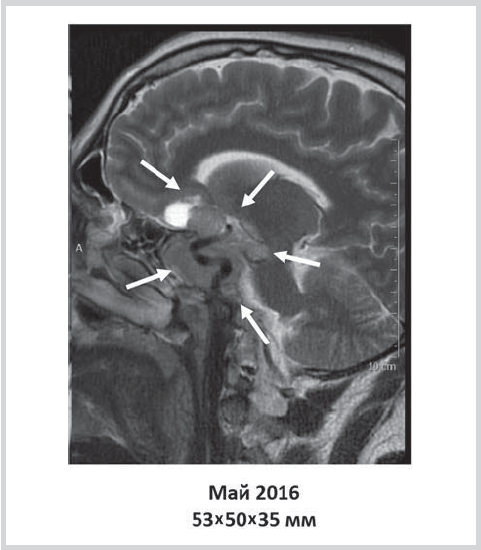

Six months after initiation of the therapy with dopamine agonists, the patient reported a decrease in headache and a significant improvement in the overall well-being. According to the brain MRI, there was a positive trend in the form of a decreased size of the formation to 53×50×35 mm (fig. 2).

Fig. 2. Change in the size of pituitary formation 6 months after cabergoline therapy.